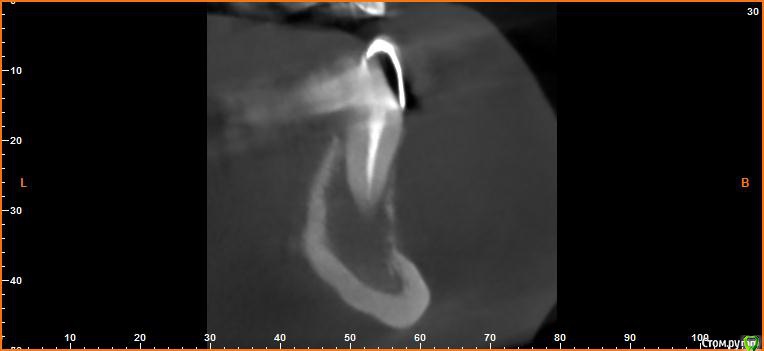

Evikrol Опубликовано 14 октября, 2015 Поделиться Опубликовано 14 октября, 2015 (изменено) Под мостовидным протезом нашли кисту. Хотим сохранить конструкцию перелечив 43 через коронку, ну и 44 тоже. А так же хотим вскрыть вестибулярную стенку кисты, провести кюретаж, промыть хлоргексидином. Дренаж ставить, нет? И вообще какой протокол правильный? Изменено 14 октября, 2015 пользователем Evikrol Ссылка на комментарий

Evikrol Опубликовано 15 октября, 2015 Автор Поделиться Опубликовано 15 октября, 2015 Поступил в гос с отёком нижней челюсти справа. Хирург сделал разрез, поставил дренаж. На прицельном сперва ничего не поняли, на кт видно что в очаг деструкции вовлечены три зуба. Сейчас уже в нашей клинике проводим эндо 43,44 и планировали провести кюретаж полости кисты. Думаете не надо?Да на кт не чётко видно границы очага, это самый информативный срез. Ссылка на комментарий

DoctorT Опубликовано 16 октября, 2015 Поделиться Опубликовано 16 октября, 2015 Не боитесь, что челюсть сломаете при такой то кисте? Кортикалка расплавлена. Мост снять, подвижность зубов оценить. Перелечить. Кисту оперировать и заполнить костнозамещим материалам. Все это под вопросом тк КТ не информативно. Ссылка на комментарий